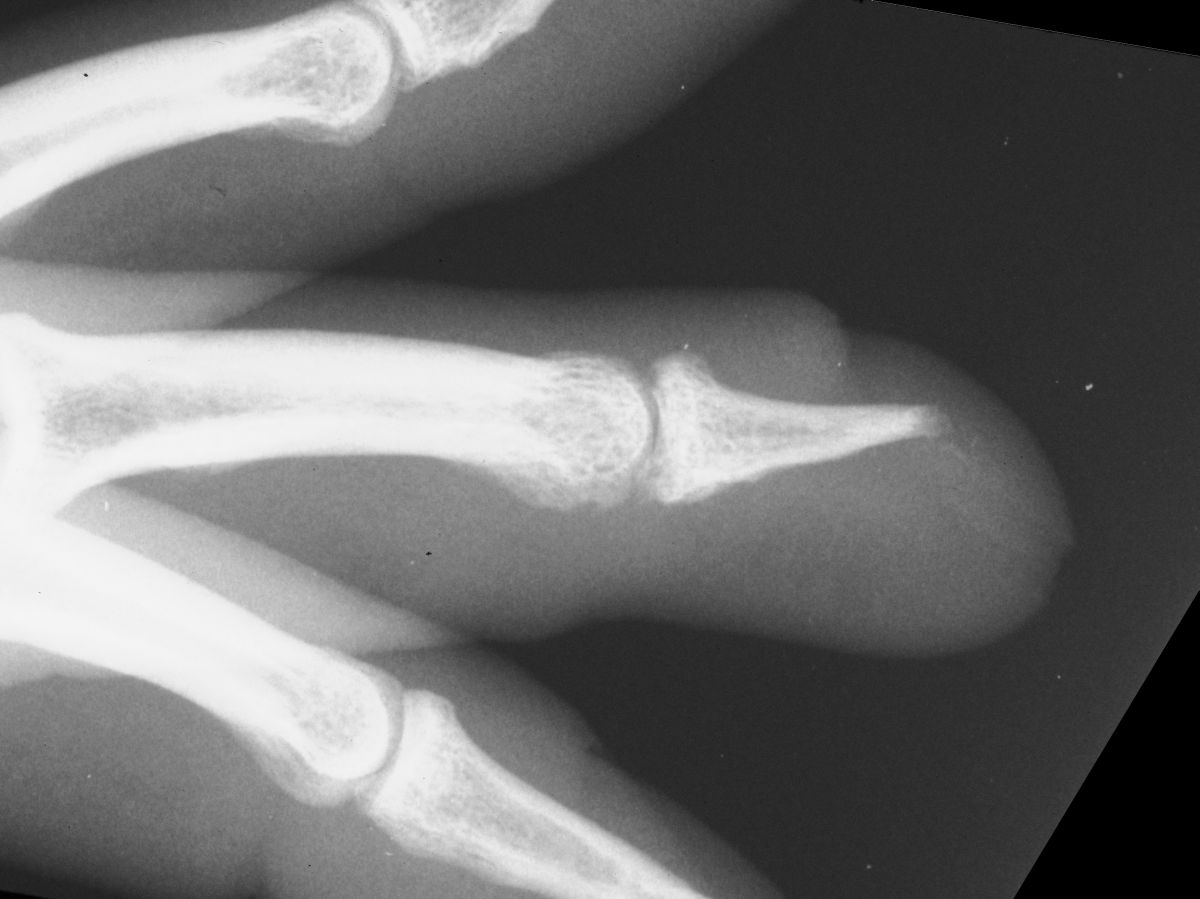

| Case

4. A dog bit off this young man's index fingertip. Although the PA Xray looks as though the bone was kept, additional views show an amputation through the tuft. |